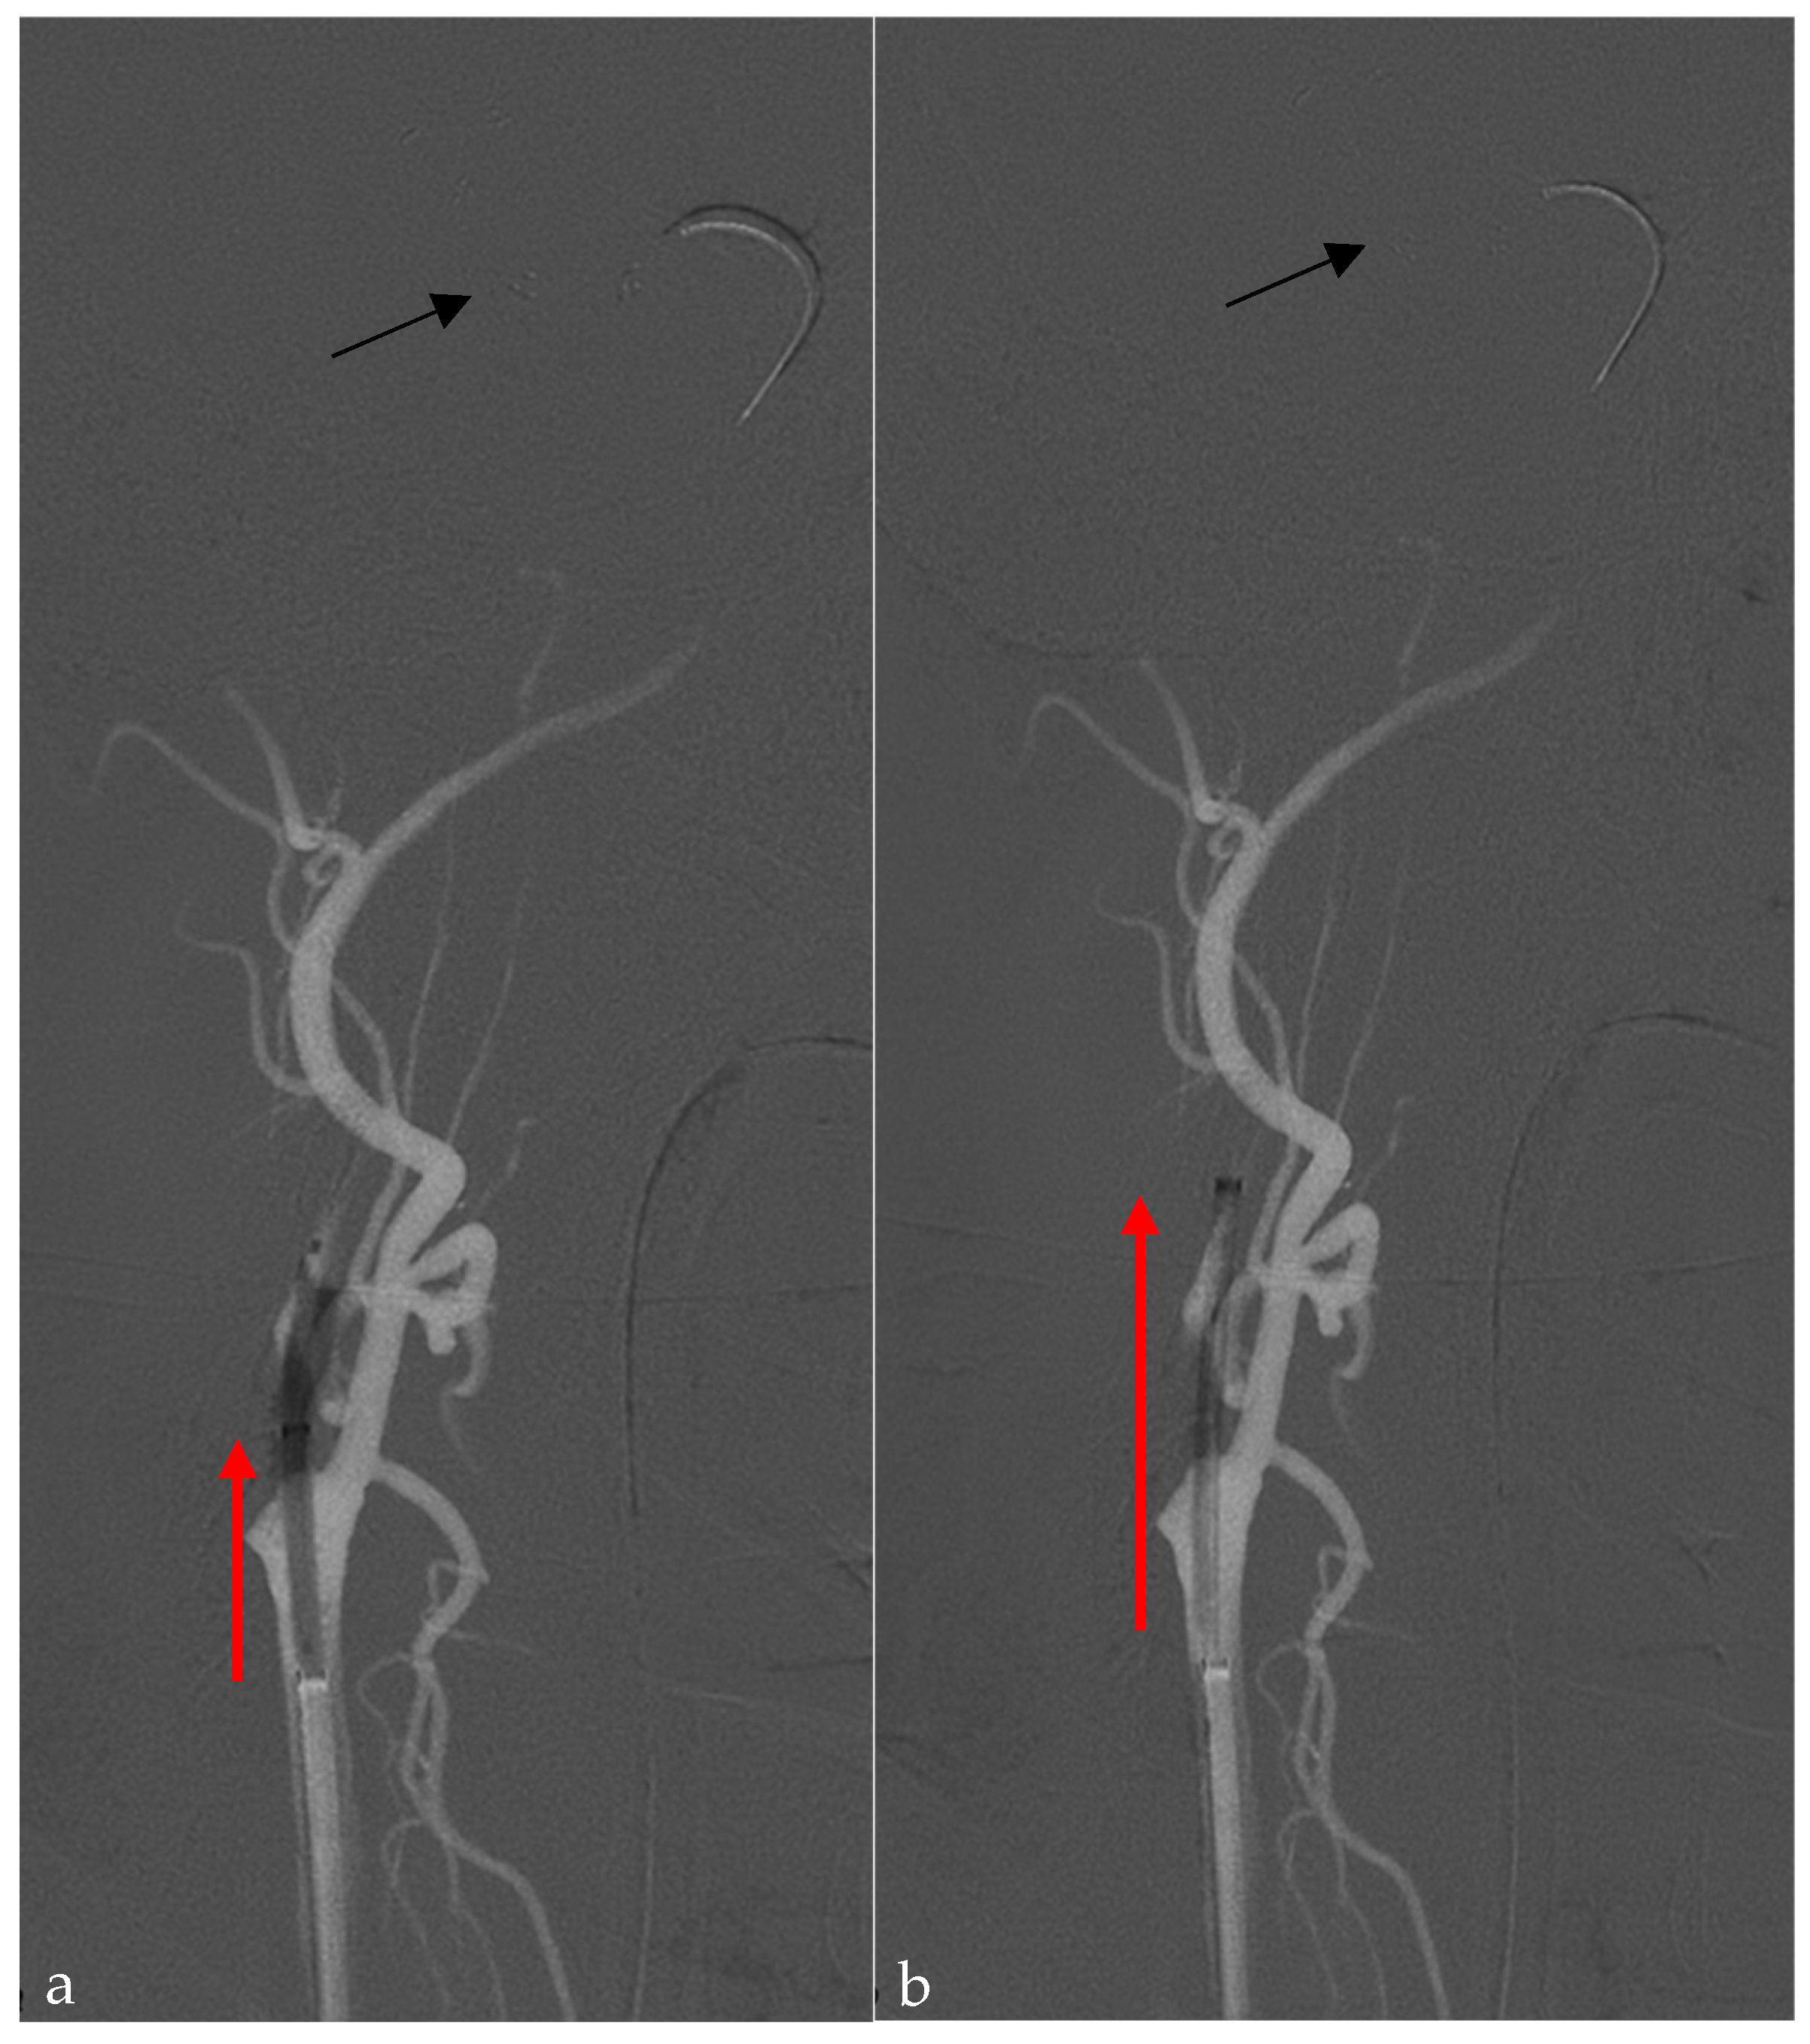

2.2. Endovascular Technique